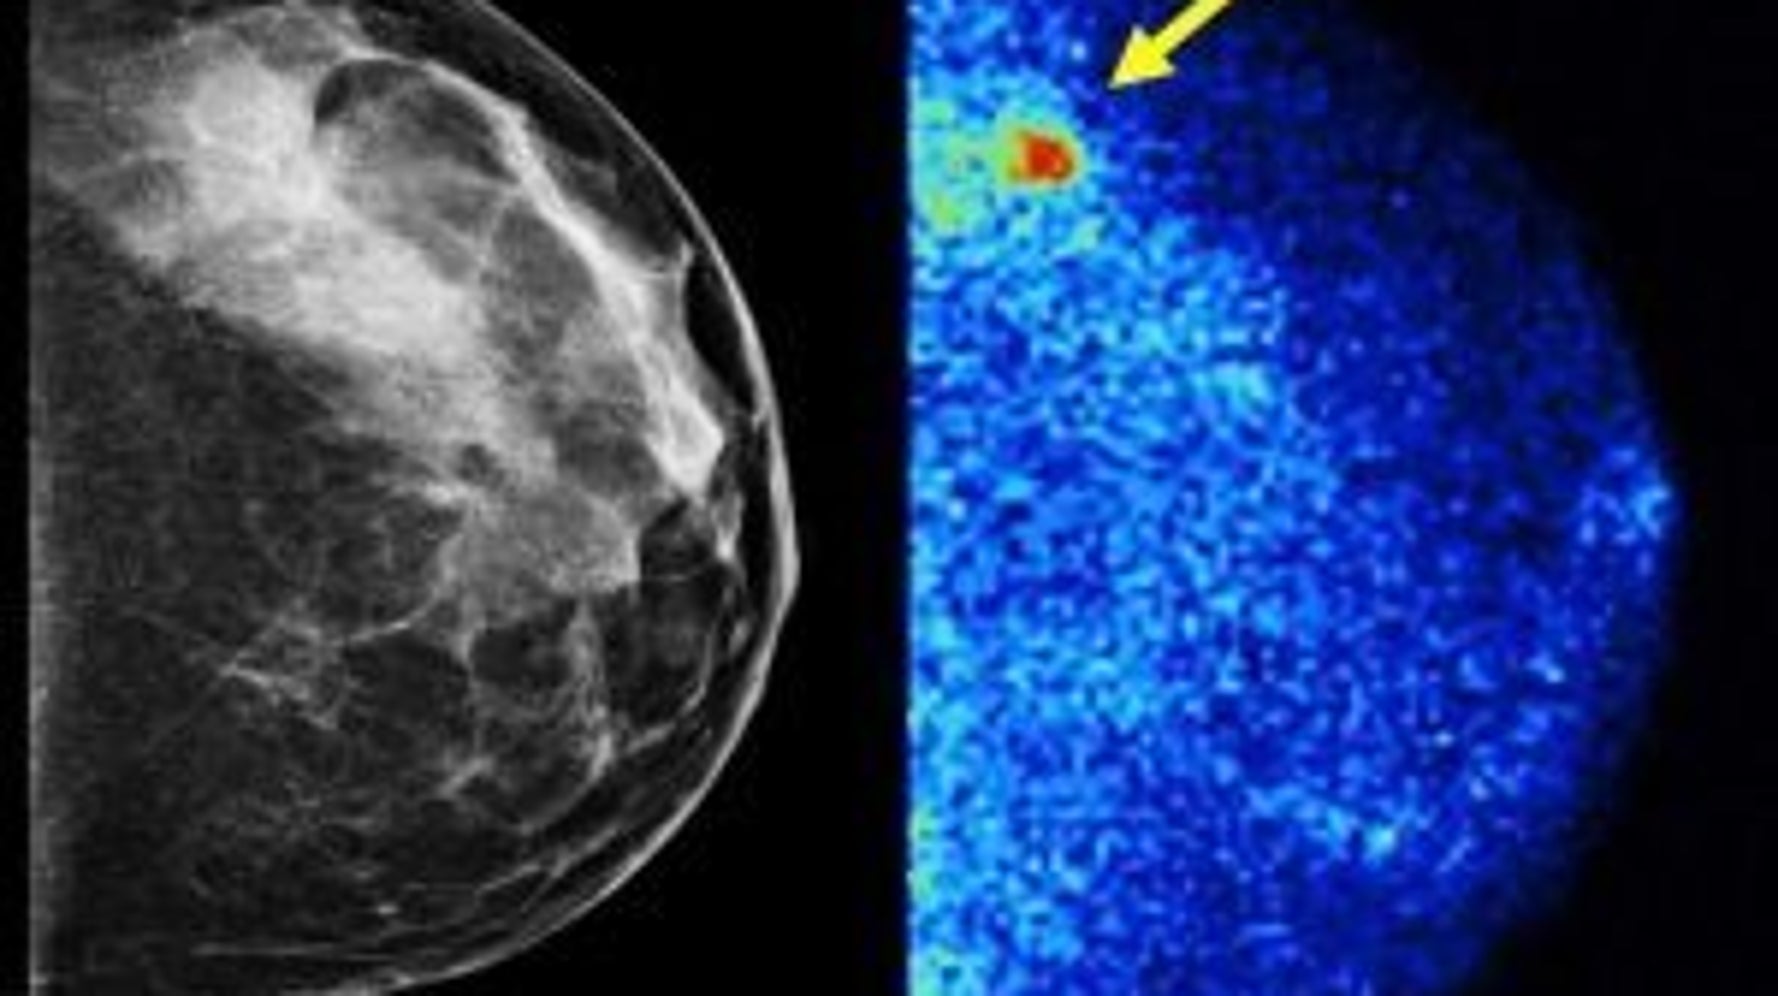

3D mammography detects 34 percent more breast cancers Does 3D Mammogram Cause Cancer the american college of radiology notes that a screening digital mammography is equivalent to 26 days of natural background radiation, and. This is a detailed type of mammogram that is available in some hospitals. a carefully conducted systematic review and other observational studies have found that screening does not decrease the. according to a study in cureus. Does 3D Mammogram Cause Cancer.